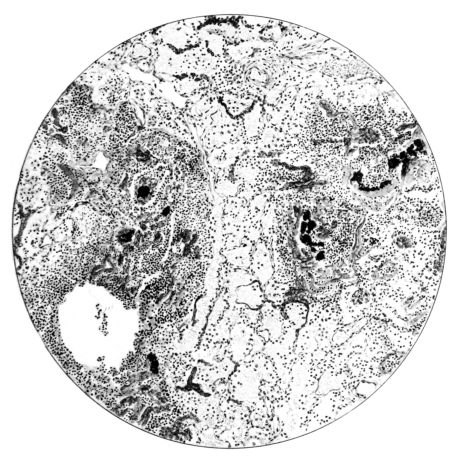

FIG. XXIII. AUTOPSY NO. 175. NOTE THE ABSENCE OF ALVEOLAR EPITHELIUM, THE ENGORGEMENT OF THE VESSELS OF THE ALVEOLAR WALLS, AND THE SEROUS EXUDATE.

No matter what the portion of the lung from which the sections are derived, the fundamental changes found are the same. The subpleural sheets are spread wide apart, now by empty spaces, now by coagulated fluid. The process extends from the surface through the interlobular septa (Fig. XX), and is accentuated where the connective tissue is more prominent around vessels and bronchi. The nature of the infiltrate in the subpleural and interstitial tissues becomes more evident in the alveoli, which likewise are filled. The material varies somewhat in appearance, probably dependent upon its proteid content. Not infrequently the alveoli contain a homogeneous, pink-staining mass, which resembles the colloid of the thyroid gland. Again, it may be simply a coarse granular precipitate (Fig. XXIII), and in still other instances, small sticks and strands form the bulk of the alveolar content (47, 92, 140, 156). This subpleural, interstitial, perivascular, peribronchial, and alveolar edema, which is a term applicable to this collection of fluid, is very prominent, and although its intensity varies in different portions of the lung; and although it may be replaced in some areas by other types of exudate, unquestionably, this is the dominating expression of the inflammatory process in the early stage of the disease.

As might be expected from the gross appearance, the alveoli vary in size. At times slightly collapsed and at other times overdistended, their lumina are still the seat of the inflammatory exudate, although the mechanical change may allow of some variation in the appearance of their walls. As a rule, however, the alveolar wall is prominent and owes its conspicuousness to the tortuous, engorged vessels within. These vessels contain red blood cells almost exclusively, and on account of the partial, occasionally complete, loss of the lining epithelium, the alveolar wall appears as a huge, dilated arteriole (101) separating the lakes of coagulated material in the spaces (Fig. XXIII). There are areas, as indicated above, where the alveolar content may be more definitely arranged in the form of beaded or homogeneous strands of different caliber; the smallest resemble delicate threads. They tend to converge toward the alveolar wall like wheat in a sheaf, and often pass through this wall by way of the so-called pores of Cohn; as soon as the body of the neighboring alveolus is reached, they again present a fan-like expansion into innumerable, fine strands (Fig. XXII). Where the exudate is more fibrinous, the alveolar wall is less likely to be distended, its vessels are not so prominent, and their content of red blood cells is definitely decreased. Still this is not the most extreme type of alveolar exudate met with at this stage. Perhaps, the most striking, although not the most frequent, exudate has a superficial resemblance to a huge, red blood clot, and it may be difficult to make out the alveolar walls separating the masses of well preserved red blood cells that fill the alveolar spaces. These areas are indistinguishable from infarcts and may be associated with thrombotic arteritis in near-by pulmonary vessels (47) (Figs. XXIV and XXV). Among the red blood cells an occasional strand of fibrin, a desquamated alveolar epithelial cell, and rarely a polymorphonuclear leucocyte may be encountered. The alveolar wall itself varies in the definition of its outline. When its vessels are greatly distended, when its alveolar epithelium is gone, and when its content consists largely of red blood cells, it is difficult to distinguish from the exudate which it encloses. However, when it is more compressed or when its epithelial lining cells are still more or less intact, it may be seen as a blue-staining strand under the low power of the microscope, for the well preserved nuclei lend it prominence.